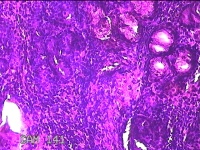

左侧鼻腔病变组织

性别

男

年龄

28岁

临床诊断

1.慢性鼻窦炎 2.鼻中隔偏曲 3.变应性鼻炎

一般病史

反复鼻塞10余年,加重伴脓涕3天。

标本名称

大体所见

灰白暗红色组织0.8x0.3x0.2cm一块,表面糜烂,内有少许骨质。